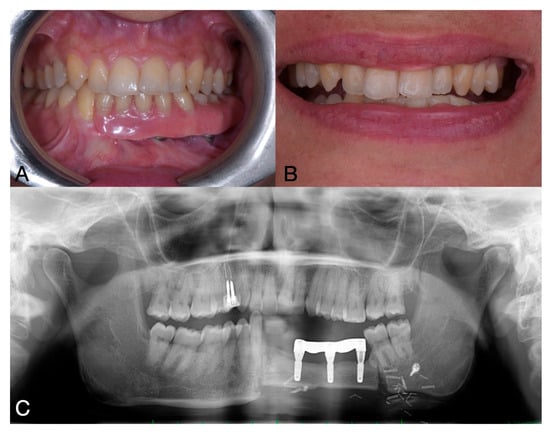

2. Case Report